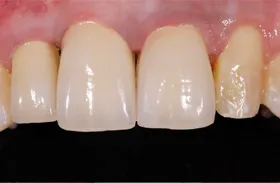

むし歯による前歯欠損の為来院されたケース

治療のポイント

歯の根の位置を引き上げ、抜歯。その日にインプラント治療へ。

自然の歯と変わらない審美性を取り戻し、非常に満足されています。

| 主訴 | 上顎の真ん中の歯が折れた |

| 治療方法 | 歯の根を引き上げることにより、増骨するので、その後1本のインプラントを埋入し治療した |

| 治療期間 | 約1年 |

| 通院回数等 | 10回 |

| 費用 | 550,000円(税込) |

| リスク・副作用 | 外科治療なしで増骨させた為、治療期間が長くなった |